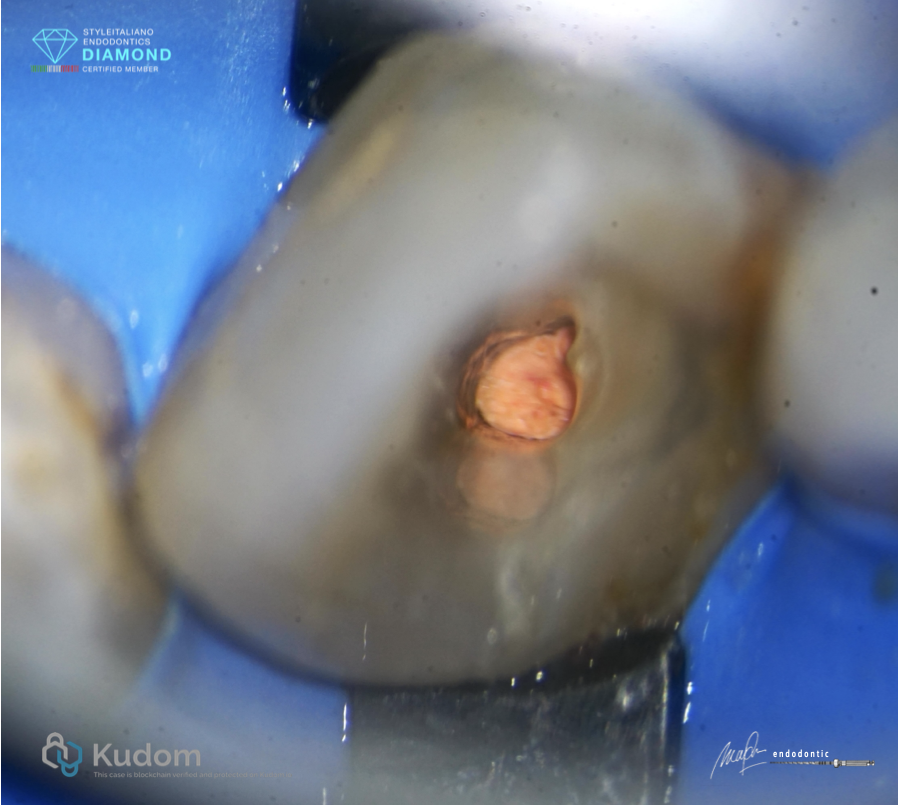

Fig. 1

Patient was referred for endodontic treatment on tooth 22, There was a quite large lesion on the apical. Leaking of coronal restorations was also noted.